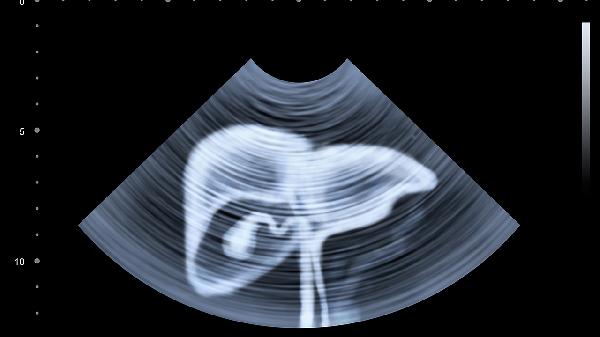

3、超声检查

经阴道超声最早在孕5周可见妊娠囊,腹部超声需延迟1-2周。超声能确认宫内妊娠、排除宫外孕,孕7周后可见胎心搏动。检查前需憋尿使膀胱充盈,但阴道超声无须特殊准备。超声检查对胎儿无辐射风险,是评估胚胎发育的重要方式。